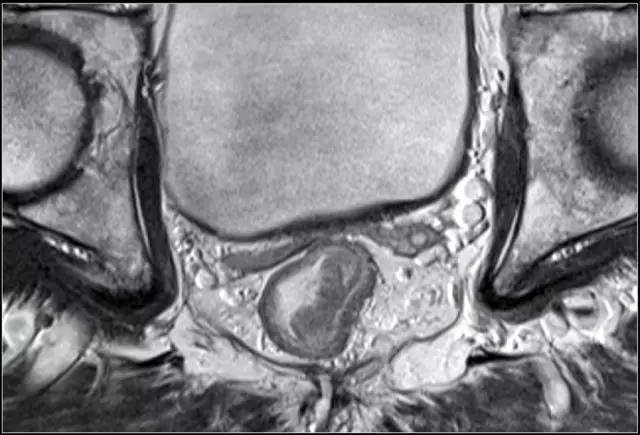

图 5 远端直肠半圆形 T2 肿瘤,与外部肌层分界明显